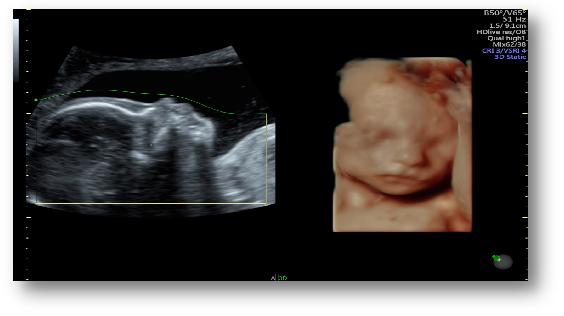

梦想系列煊光E8优异的基础图像质量、创新的容积成像模式和分析处理技术,诸如:SRI II斑点噪声抑制成像、CrossXBeam CRI实时空间复合成像、HD-Flow超高细微分辨血流成像技术、HDlive高分辨容积成像技术、VCI高级容积对比成像模式和OmniView自由解剖成像、TUI断层超声显像等创新技术结合专业的自动化成像与诊断工具SonoRenderlive实时自动胎儿追踪成像、SonoNT自动胎儿颈后透明层厚度测量、SonoIT自动胎儿颅内透明层测量、SonoBiometry自动胎儿生长指标测量等。上述技术为产前超声筛查与诊断提供了业绩最完整的系统解决方案。

SonoRenderlive实时自动胎儿追踪成像——快速、实时、精确,自动调整绿线位置实现最佳渲染效果,容积成像智能化。4D模式下实时自动追踪胎儿运动,智能调整。

产科领域:具有2D-4D的优良图像质量,可以实时立体直观动态地检测胎儿,具有排查胎儿畸形准确,照片清晰的特点。对于11-14周胎儿NT值测量、中晚期胎儿的排畸筛查更准确性,尤其针对唇腭裂、腹壁畸形、胎儿中枢神经系统、骨骼、心脏畸形等胎儿畸形的排查更具优越性。